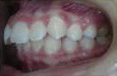

- 矯正治療開始前,

- 要進行一些簡單的常規檢查與記錄,了解口腔與牙齒的情況:

- a. 口內及顏面外觀照相記錄。